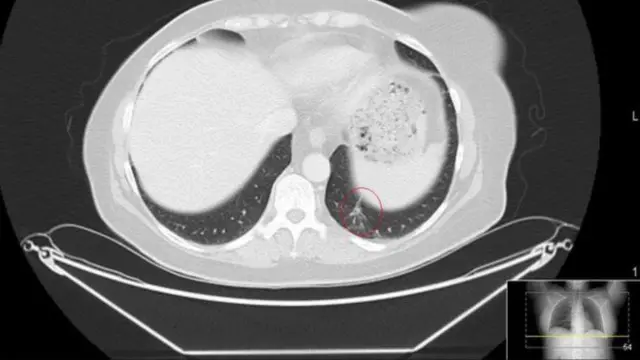

وصنف الورم الذي أصاب وجهها بأنه ورم حميد لكنه في الحقيقة كان ورما سرطانيا وانتشر إلى الرئة. وقال الأطباء إنها ستعيش فقط ما بين 18 إلى 24 شهرا.